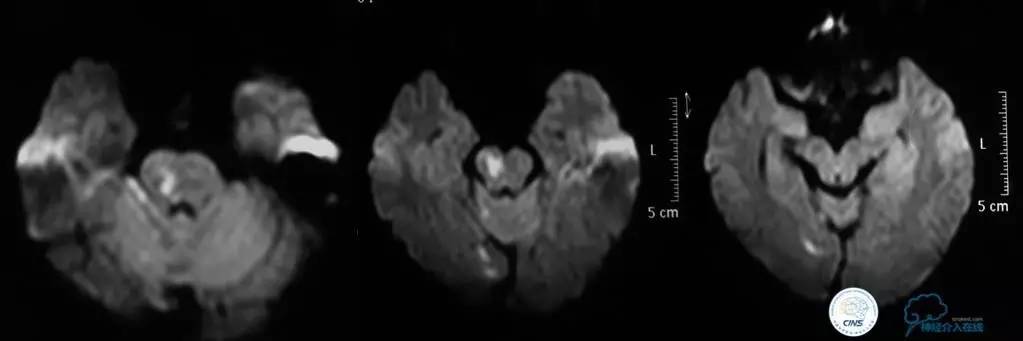

▼2015-06-05颅脑MRI

▼颅脑CT

▼2015-06-13颅脑CT

患者症状稳定,遗留有失语及右侧肢体活动不灵。